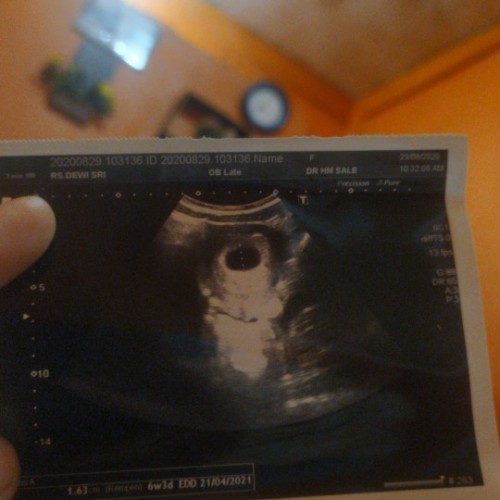

aku usg pas 6w

5week mom, baru kantung